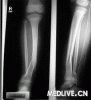

四肢长管状骨骨折

病例摘要:男性,20岁,车祸后左小腿疼痛1小时。 患者驾驶小轿车与前车追尾,伤后神志清楚,无恶心呕吐,无皮肤活动出血及四肢麻木。由救护车送往医院。 查体:神志清楚,面色口唇苍白,BP 80/50mmHg,R ll0次/分,心肺腹检查未见异常。 专科情况:左小腿肿胀明显,可及骨擦音及骨擦感。左大腿皮肤感觉正常,足背动脉搏动弱。 血常规示Hb 92g/L,WBC 7.8×10 9/L,PLTl02×109/L。